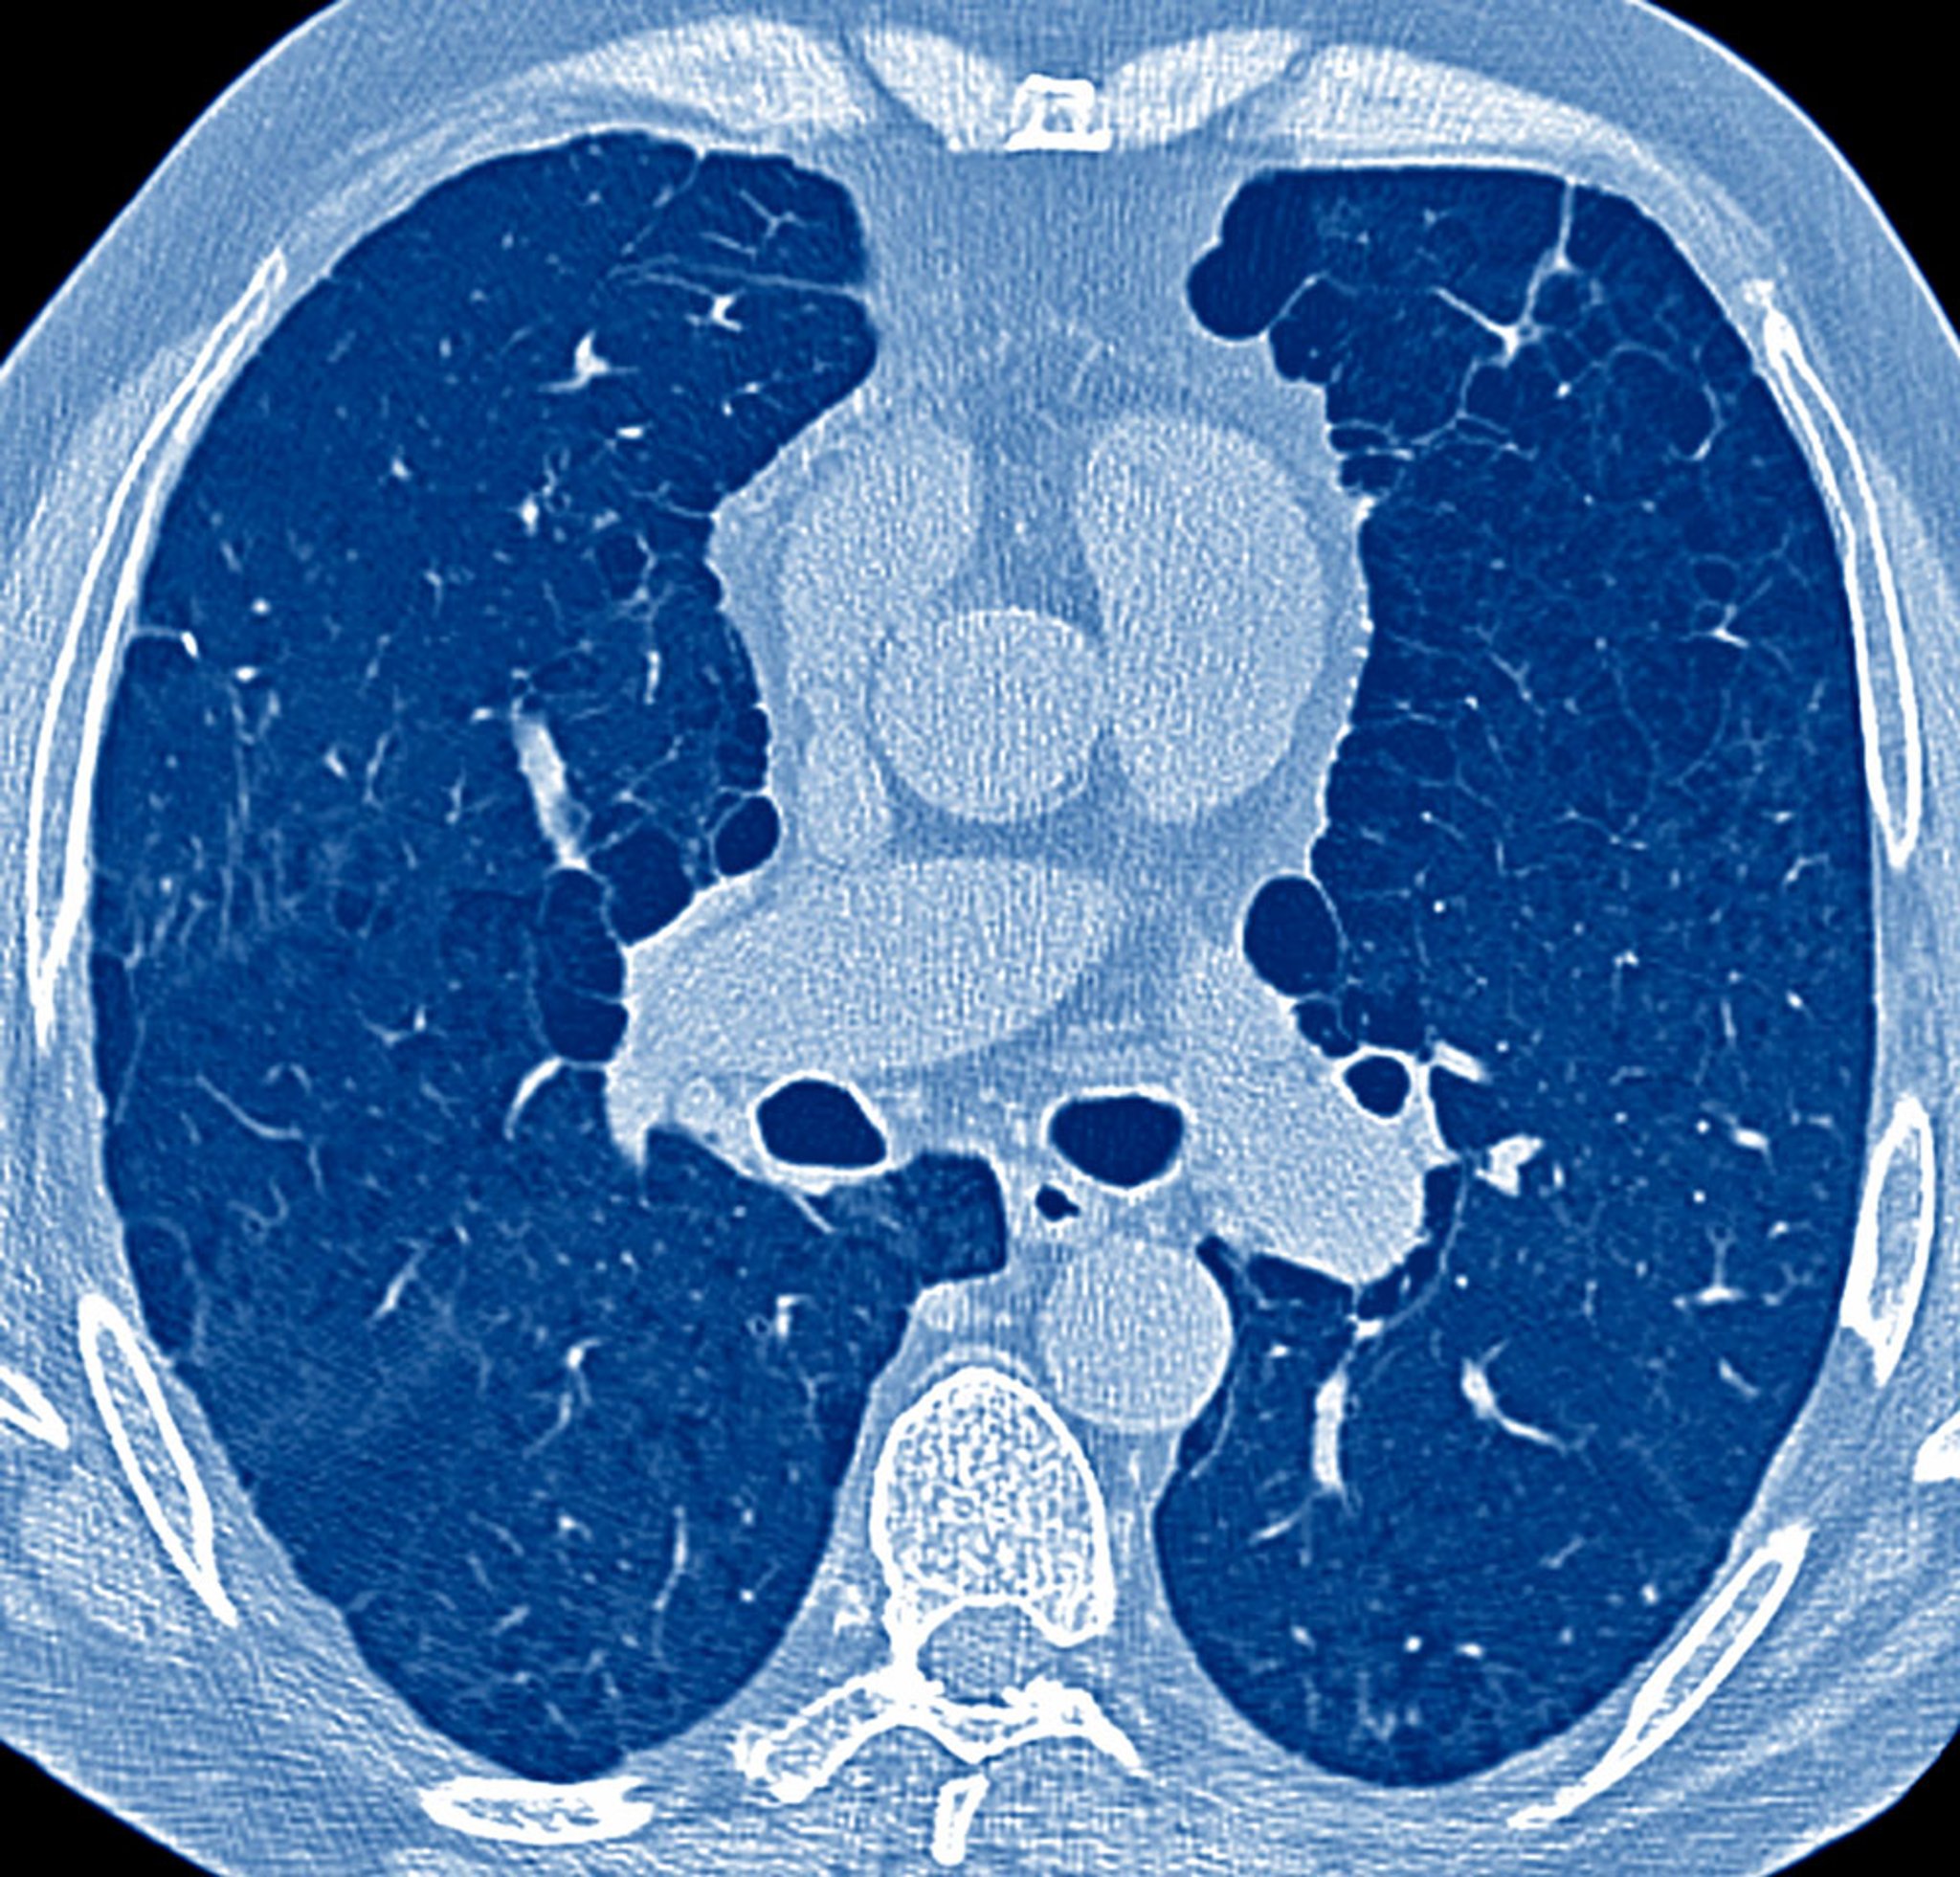

Die wichtigsten diagnostischen Schritte bei Patienten mit pulmonalen Symptomen bilden Anamnese, körperliche Untersuchung und in vielen Fällen eine Röntgenthoraxaufnahme. Diese Komponenten machen nachfolgende Tests erforderlich, die Lungenfunktionstests, arterielle Blutgasanalyse (ABG), Thorax-CT und andere Thorax-Bildgebungstests, Echokardiographie, 6-Minuten-Gehtest, kardiopulmonale Belastungstests, Rechtsherzkatheterisierung, Bronchoskopie, und Lungenbiopsie umfassen können.